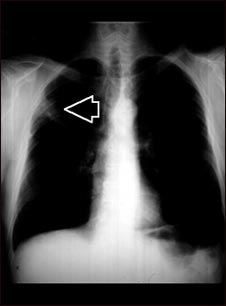

Masa pulmonar, pulmón superior derecho - Radiografía de tórax

Radiografía del tórax de una persona con una masa pulmonar. Esta es una vista frontal, donde los pulmones son las dos áreas oscuras y el corazón y las otras estructuras son visibles en el centro del tórax. La radiografía muestra una masa en la parte superior del pulmón derecho, marcada por una flecha (al lado izquierdo de la imagen).